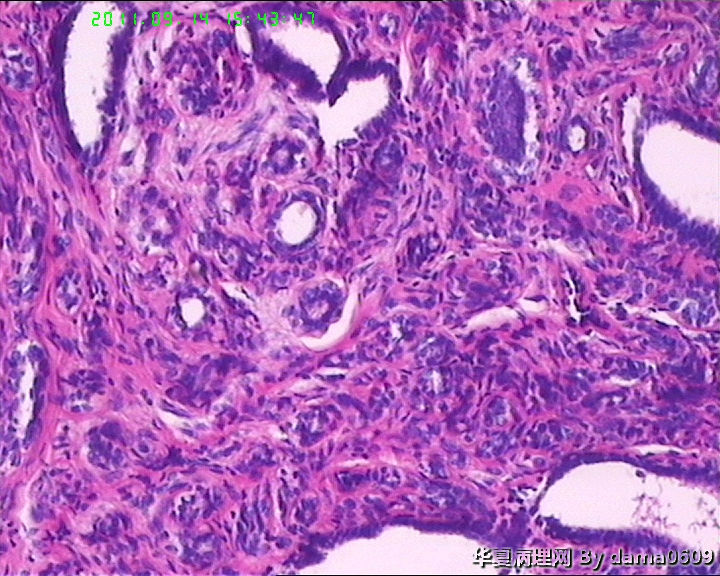

女,22岁,乳腺肿物,病史不详。

不整形软组织肿物一个,V:2.0x1.5x1.5cm。无包膜。切面实性,灰白色,小结节状,质中。

镜下结构复杂,图3、4、8、10、11、12、13、15、17、18、19、20为肿物中央区域,占标本大部分,图1、2、7、14为肿物边缘部分,图5、6、9、16、21为二者交界处。有点乱,不好意思,请老师别介意。

请教老师,诊断:硬化性腺病,可以吗??谢谢!!